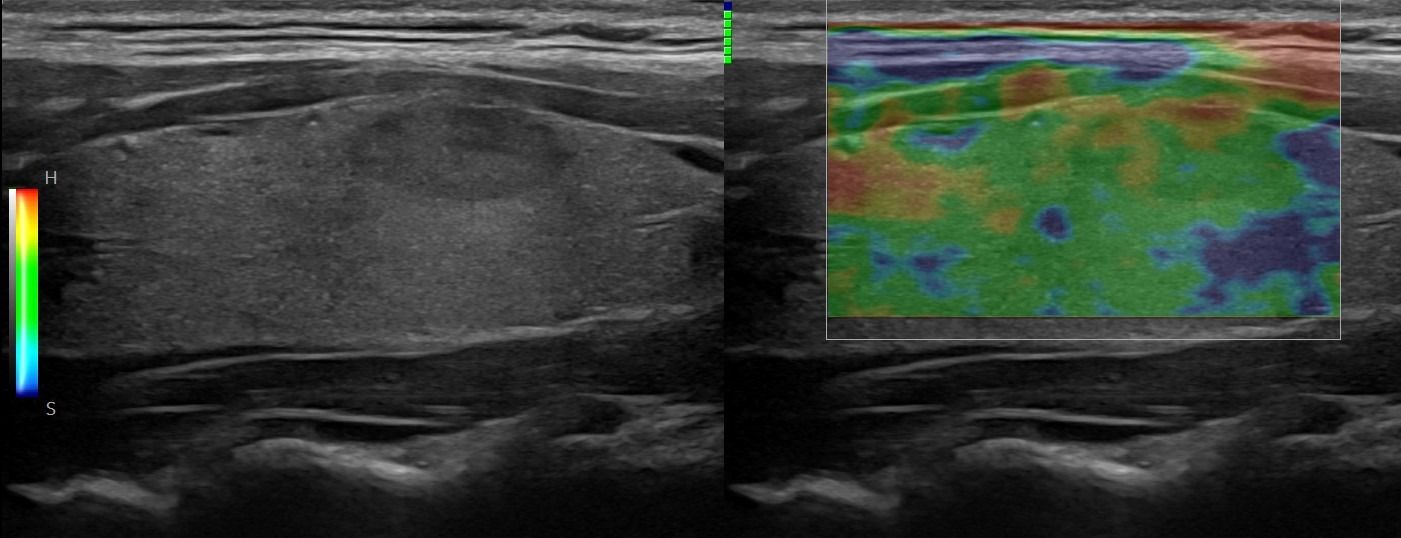

Με την τριπλή μελέτη του Θυρεοειδούς Αδένα, που περιλαμβάνει το B-Μode, το Έγχρωμο Υπερηχογράφημα και την Ελαστογραφία, γίνεται μια ολοκληρωμένη χαρτογράφηση του θυρεοειδούς αδένα. Το περίγραμμα, η αγγείωση και η ελαστικότητα του αδένα, καθώς και η υφή μίας πιθανής βλάβης αξιολογούνται με ακρίβεια και αξιοπιστία.